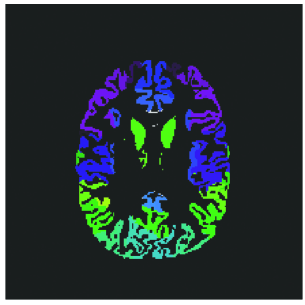

3D T1-w MRIs were pre-processed and provided by the challenge organizer. The pre-processing steps involved first creating brain masks from a series of standard brain extraction softwares including FSL BET, AFNI 3dSkullStrip, FreeSurer mri_gcut, and Robust Brain Extraction (ROBEX). The final brain mask was obtained by taking majority voting across these resulting masks. This final brain mask was used to perform bias correction and the extracted brain was segmented into brain tissue (gray matter, white matter, and cerebrospional fluid (CSF)) using Atropos. Finally the skull-stripped brain and segmented brain images were registered affinely to the SRI24 atlas [15]. Fig. 2 shows typical example of the pre-processed, skullstripped T1-w MRI and segmented brain MRI provided by the organizers.

Refer to caption

Figure 2: (a) Example of pre-processed T1-w brain MRI. (b) Example of the white matter, gray matter, and CSF segmented brain MRI of the same T1-w image.